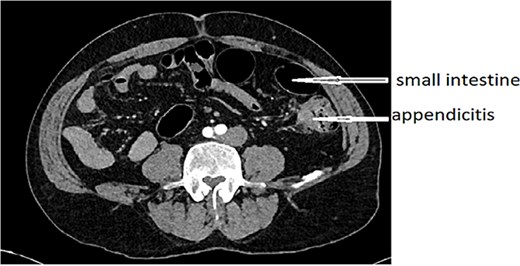

An urgent CT scan revealed situs inversus (Fig. 1) with left-sided high-positioned appendicitis (Fig. 2).